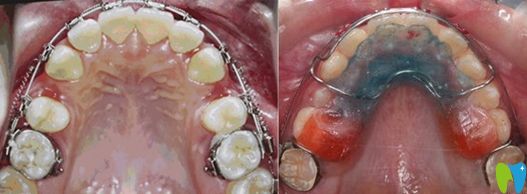

牙弓狹小需要擴(kuò)弓的病例圖

擴(kuò)弓矯正的前后效果對比圖